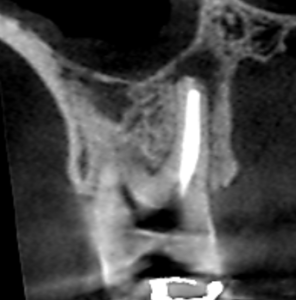

精密根管治療6カ月後の経過観察時の上顎大臼歯口蓋根の冠状断のCT画像です。

矢印の先にあった膿が消失し、歯槽骨が再生しています。